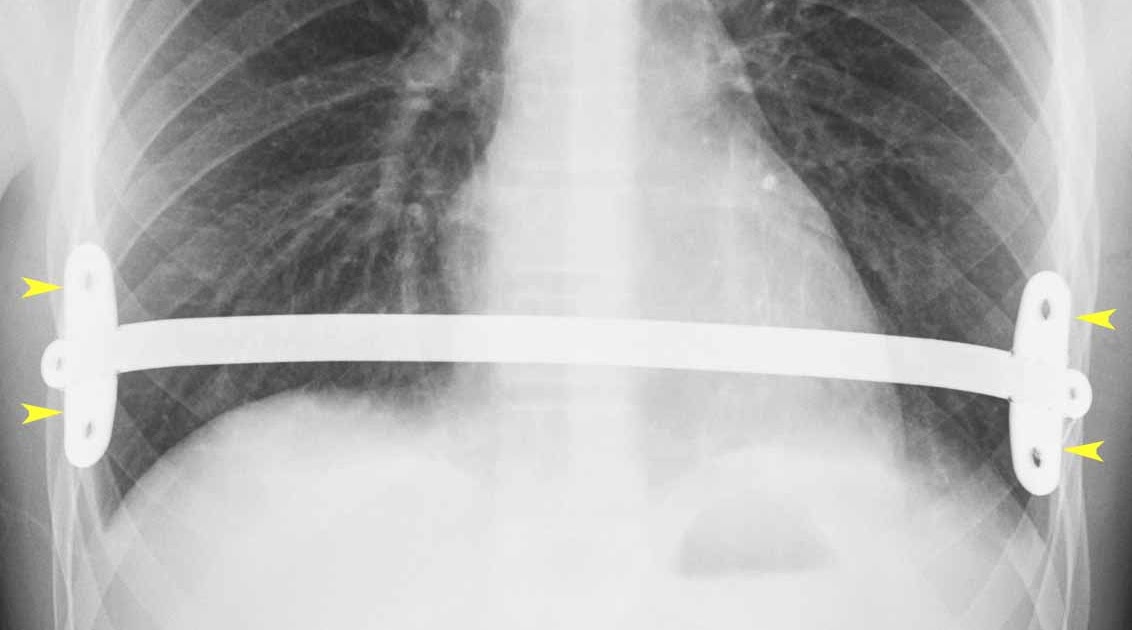

WebBackground: There are conflicting reports in the literature comparing outcomes after open Ravitch and minimally invasive Nuss procedures for pectus excavatum repair, and there. WebThe pectus bars are removed two years after insertion with minimally invasive surgeries like the Nuss procedure. It is also an outpatient process that takes.

Figure 6 from Surgical correction of 639 pectus excavatum cases via the

Source: www.semanticscholar.org